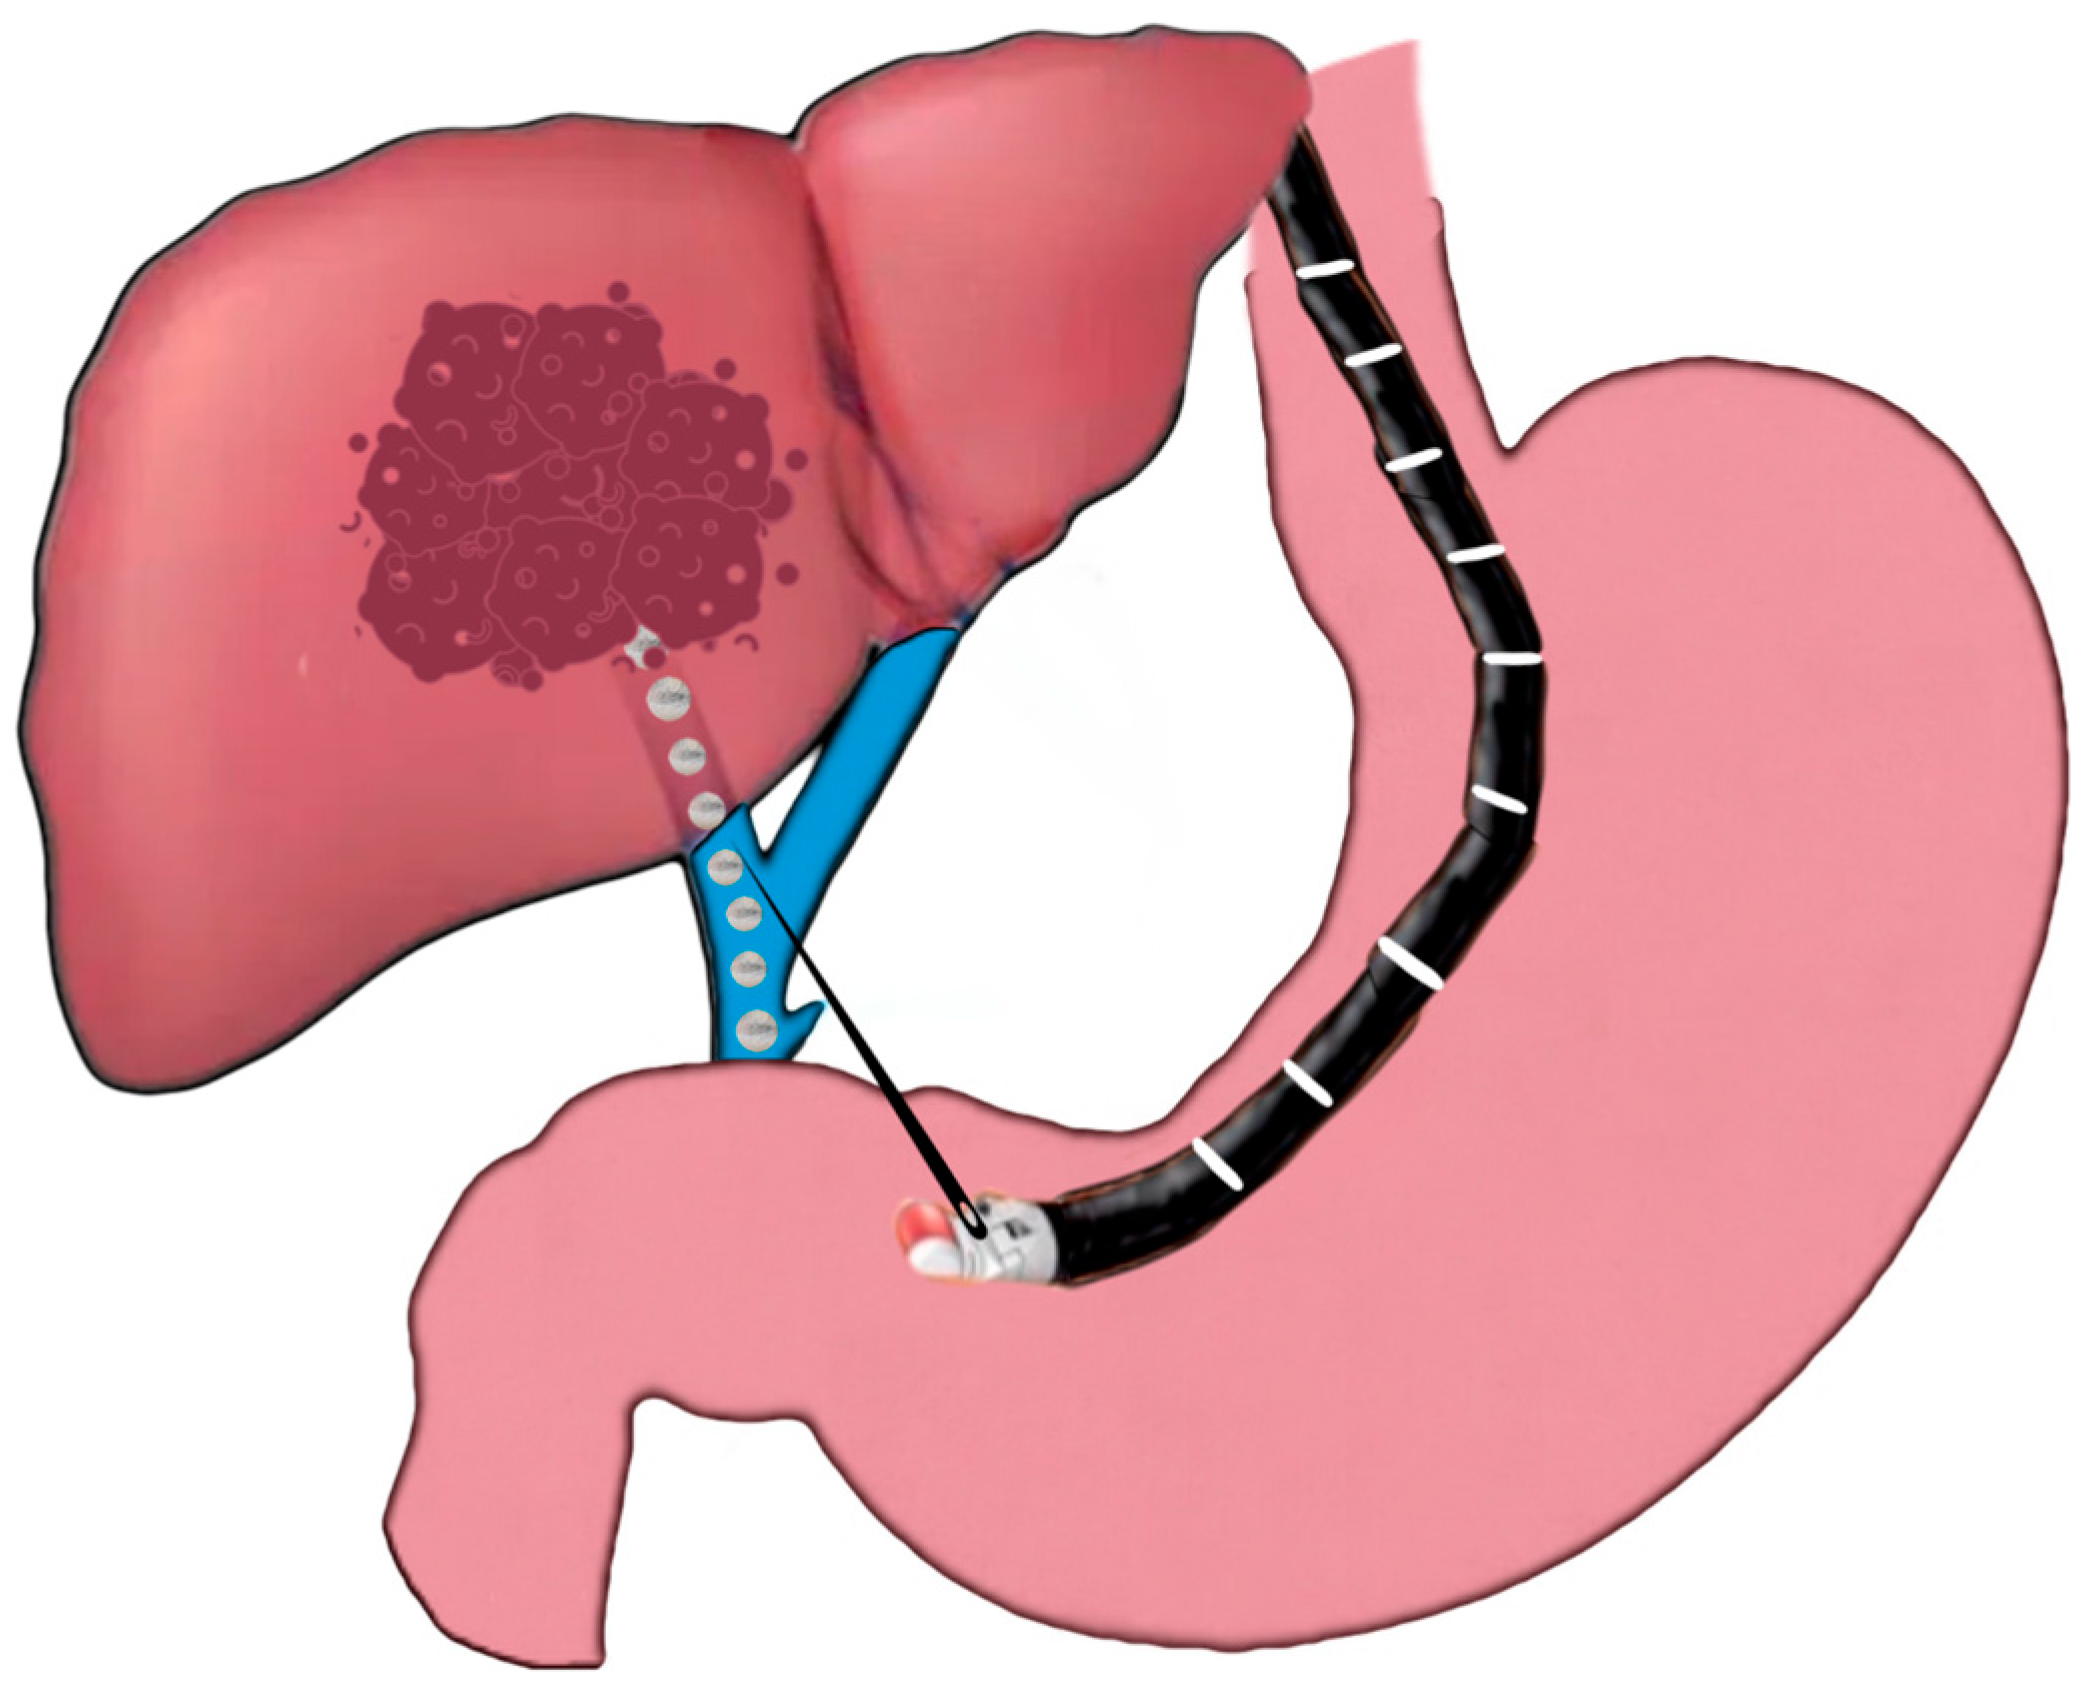

2.3.1. EUS-Guided Liver Tumor Ablation

- Wallace, M.B.; Sabbagh, L.C. EUS 2008 Working Group document: Evaluation of EUS-guided tumor ablation. Gastrointest. Endosc. 2009, 69, S59–S63. [Google Scholar] [CrossRef]

- Chua, T.; Faigel, D.O. Endoscopic Ultrasound-Guided Ablation of Liver Tumors. Gastrointest. Endosc. Clin. N. Am. 2019, 29, 369–379. [Google Scholar] [CrossRef]

- Chang, K.J.; Irisawa, A. EUS 2008 Working Group document: Evaluation of EUS-guided injection therapy for tumors. Gastrointest. Endosc. 2009, 69, S54–S58. [Google Scholar] [CrossRef]